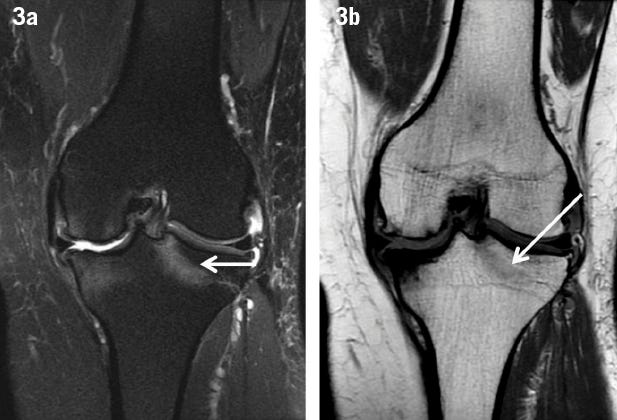

Symptoms: Deep bone pain, tenderness over ribs, pelvis, or lower spine; pain on minor pressure or movement; occasionally visible MRI edema.

Imaging: Normal radiographs but micro‑edema or trabecular stress lines on MRI or bone‑scan.